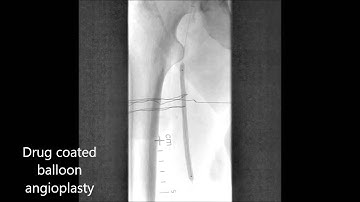

JetStream Atherectomy for In-Stent Restenotic Lesion